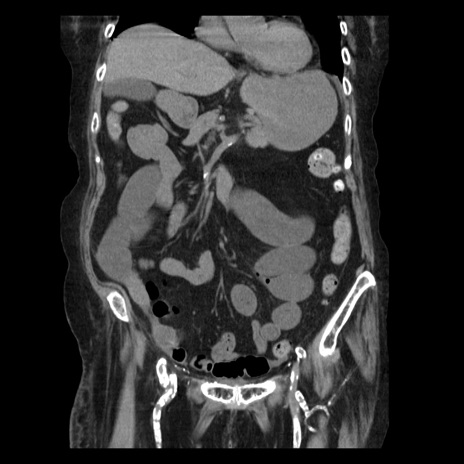

症例14(冠状断像)

【症例】 90歳代女性

【主訴】 腹痛・嘔吐

【現病歴】今朝から左側腹部痛を認めた。 経過観察していたが、嘔吐を認めたため来院。

【既往歴】 子宮癌術後

【身体所見】 意識清明、BP 127/54mmHg、P 98bpm Sp02 95%(RA)、BT 35.8°C、腹部平坦・軟腸ぜん動音聴取良好、右下腹部圧痛(+) 反跳痛なし

【データ】WBC 9800、CRP 0.46